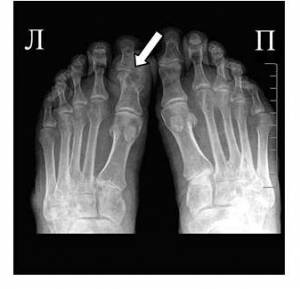

• Сделать рентгенографию сустава — чтобы исключить другие причины воспаления, например травму.

На фото симптом «пробойника» на кости первого пальца ноги